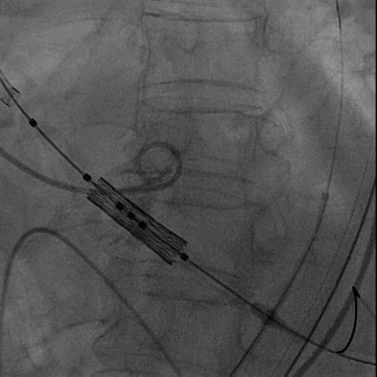

22mm球囊预扩张